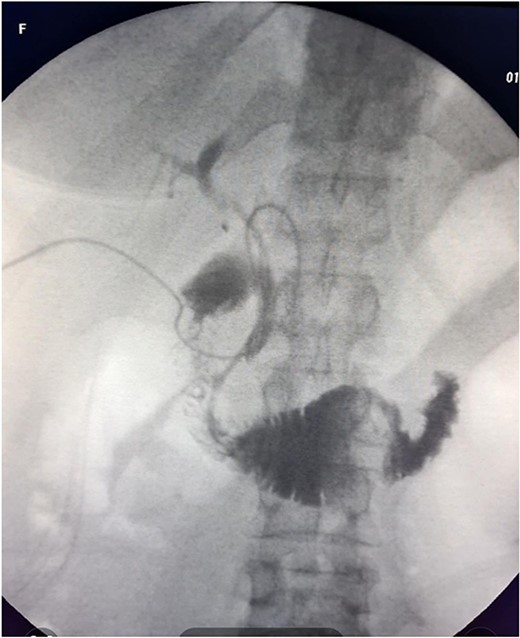

The patient was scheduled for a laparoscopic cholecystectomy the following day. Intraoperatively, an enlarged gallbladder hydrops with the presence of various caliber calculi in the lumen, the largest of which measured 2 cm/d, was found. The contents of the bladder are punctured and evacuated to facilitate its grasping in the fundus area and creating a good exposure of Callot’s triangle. Using a four trocar technique, a dissection was performed in the triangle of Callot, noting the difficult manipulation in the area between cystic duct and common hepatic duct. The cystic duct is identified to its confluence with the common bile duct at a 45° angle. The cystic artery was also visualized, after which clips were placed on both structures after ensuring that they entered the gallbladder. Dissection of the gallbladder in its distal part, attached to the liver parenchyma above Rouvier’s line, was started using electrocautery and hook. The tissue density of a limited area in the distal part between the wall of the gallbladder and the liver parenchyma was dissected using a hook. A bile duct was opened in its unusual anatomical location (Fig. 1). Due to lack of equipment for intraoperative cholangiography, it was converted to open access and subsequent revision of the extrahepatic bile ducts. The common bile duct and right–left hepatic duct were mobilized to the site of entry into the liver parenchyma. A parietal lesion of the right hepatic duct just above the confluence and anatomical integrity of the common bile duct and left hepatic duct were found. After examining the removed gallbladder, it was found that it was immediately flowing into a duct which connects the cystic duct with the right hepatic duct as depicted in Fig. 2. A plasty of the right hepatic duct was performed, and prior to this duodenotomy and papillotomy were performed by mobilization of the duodenum according to Kocher. A protective drain was placed in the choledochus draining from the right hepatic duct to the ampulla of Vater. Separetely, the clips previously placed on the cystic duct were removed and a transcystic drain was placed; a leak test was performed at the plastic site of the right hepatic duct. The postoperative period was without complications. From the transcystic drain, the secretion of bile stopped on the fourth postoperative day. On the eighth postoperative day, transdrainage cholangiography was performed; the common bile duct and bought hepatic ducts were imaged, and free passage of the contrast material through the duodenum was established (Fig. 3). The transcystic draine was removed on the 20th day of surgery.

Gallbladder (1) distal part ot the cystic duct; (2) the part connecting with the right hepatic duct; (3) entrance to cystic duct from the lumen of the gallbladder.